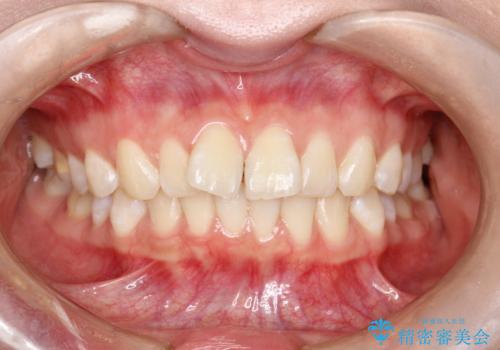

- 前歯の叢生(がたつき)を主訴に来院された患者様です。以前マウスピース矯正をされていたそうでしたが、自身での継続が難しいことなどを理由に、ワイヤー矯正にて改めて矯正治療を希望されました。非抜歯にて治療を計画し治療を行いました。

歯の動きが良く、スムーズに治療を終了しました。一般的にワイヤー矯正はブラッシングが難しいのですが、毎回一生懸命セルフケアをされていたのが印象的です。治療においては、歯の衛生状態も一緒にチェック致します。